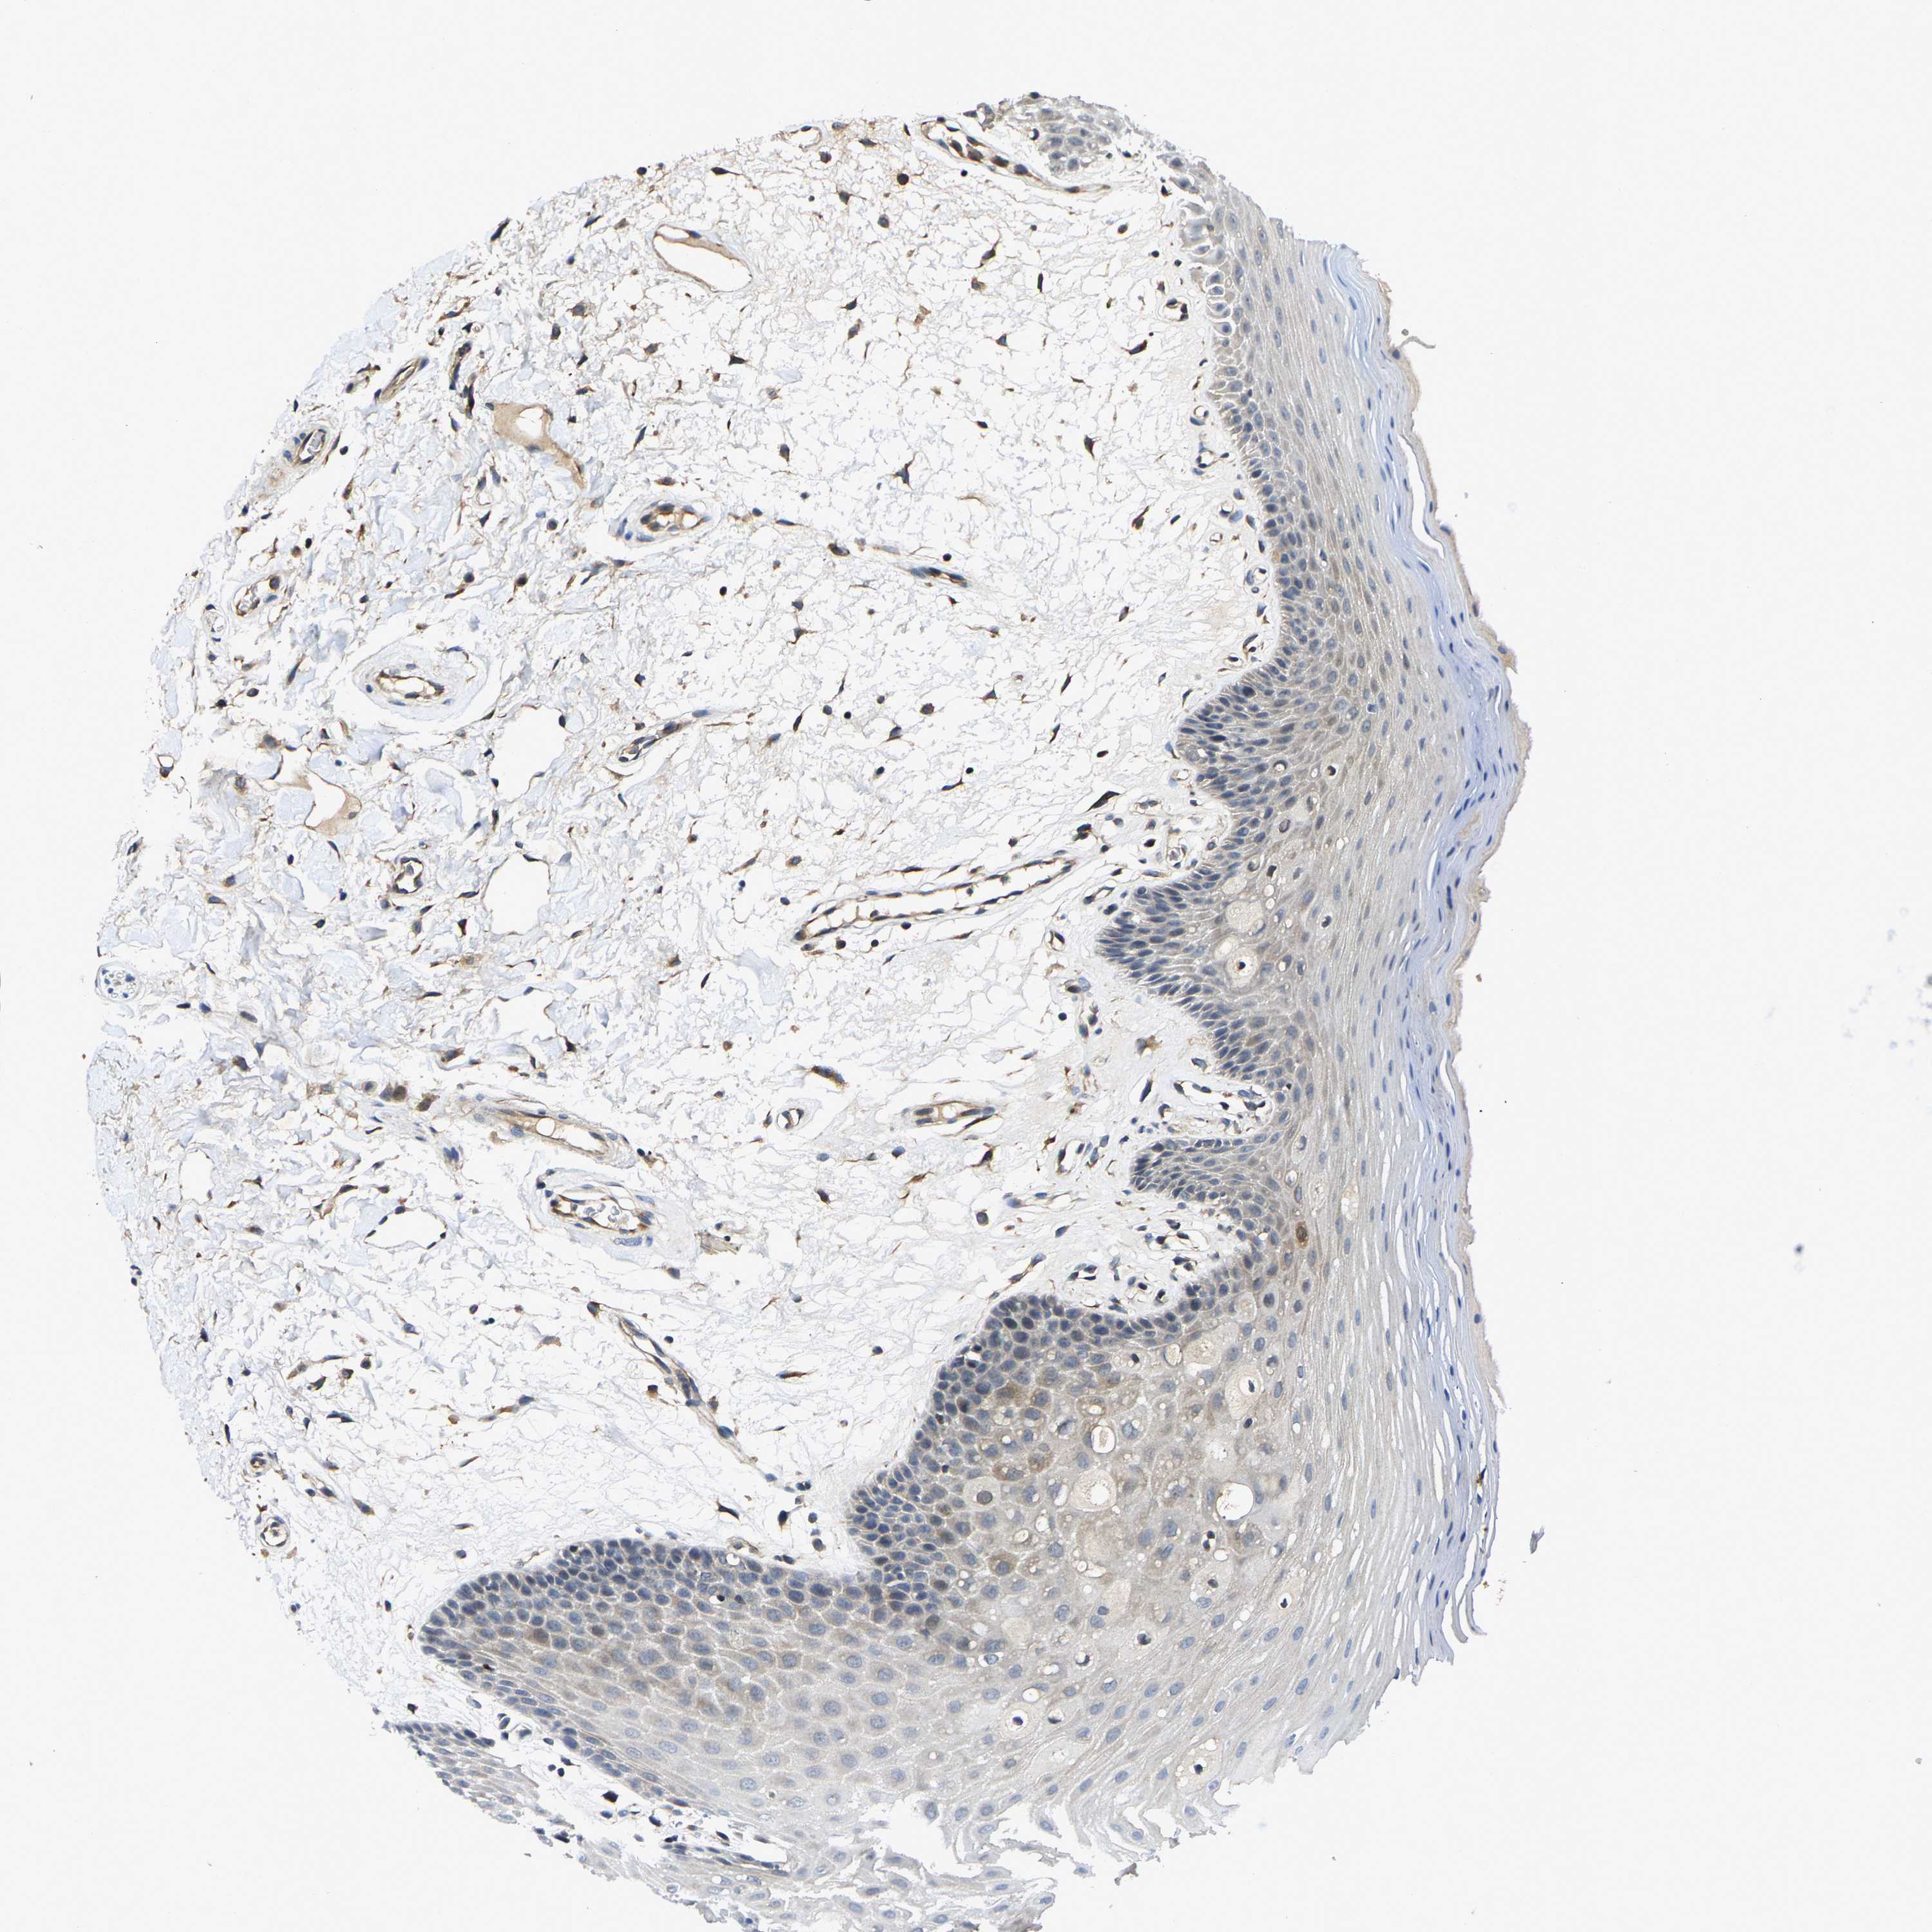

ORAL MUCOSA - Antibody stainingi

Antibody staining in the annotated cell types in the current human tissue is reported as not detected, low, medium, or high, based on conventional immunohistochemistry profiling in selected tissues. This score is based on the combination of the staining intensity and fraction of stained cells.

Each image is clickable and will lead to virtual microscopy that enables deeper exploration of all samples and also displays staining intensity scores, fraction scores and subcellular localization as well as patient and tissue information for each sample.

Antibody HPA020397Antibody HPA024150

Squamous epithelial cells Not detectedMedium